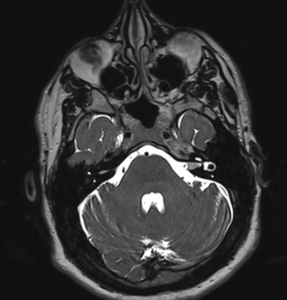

Ενδοκαναλικό Ακουστικό Νευρίνωμα αριστερά